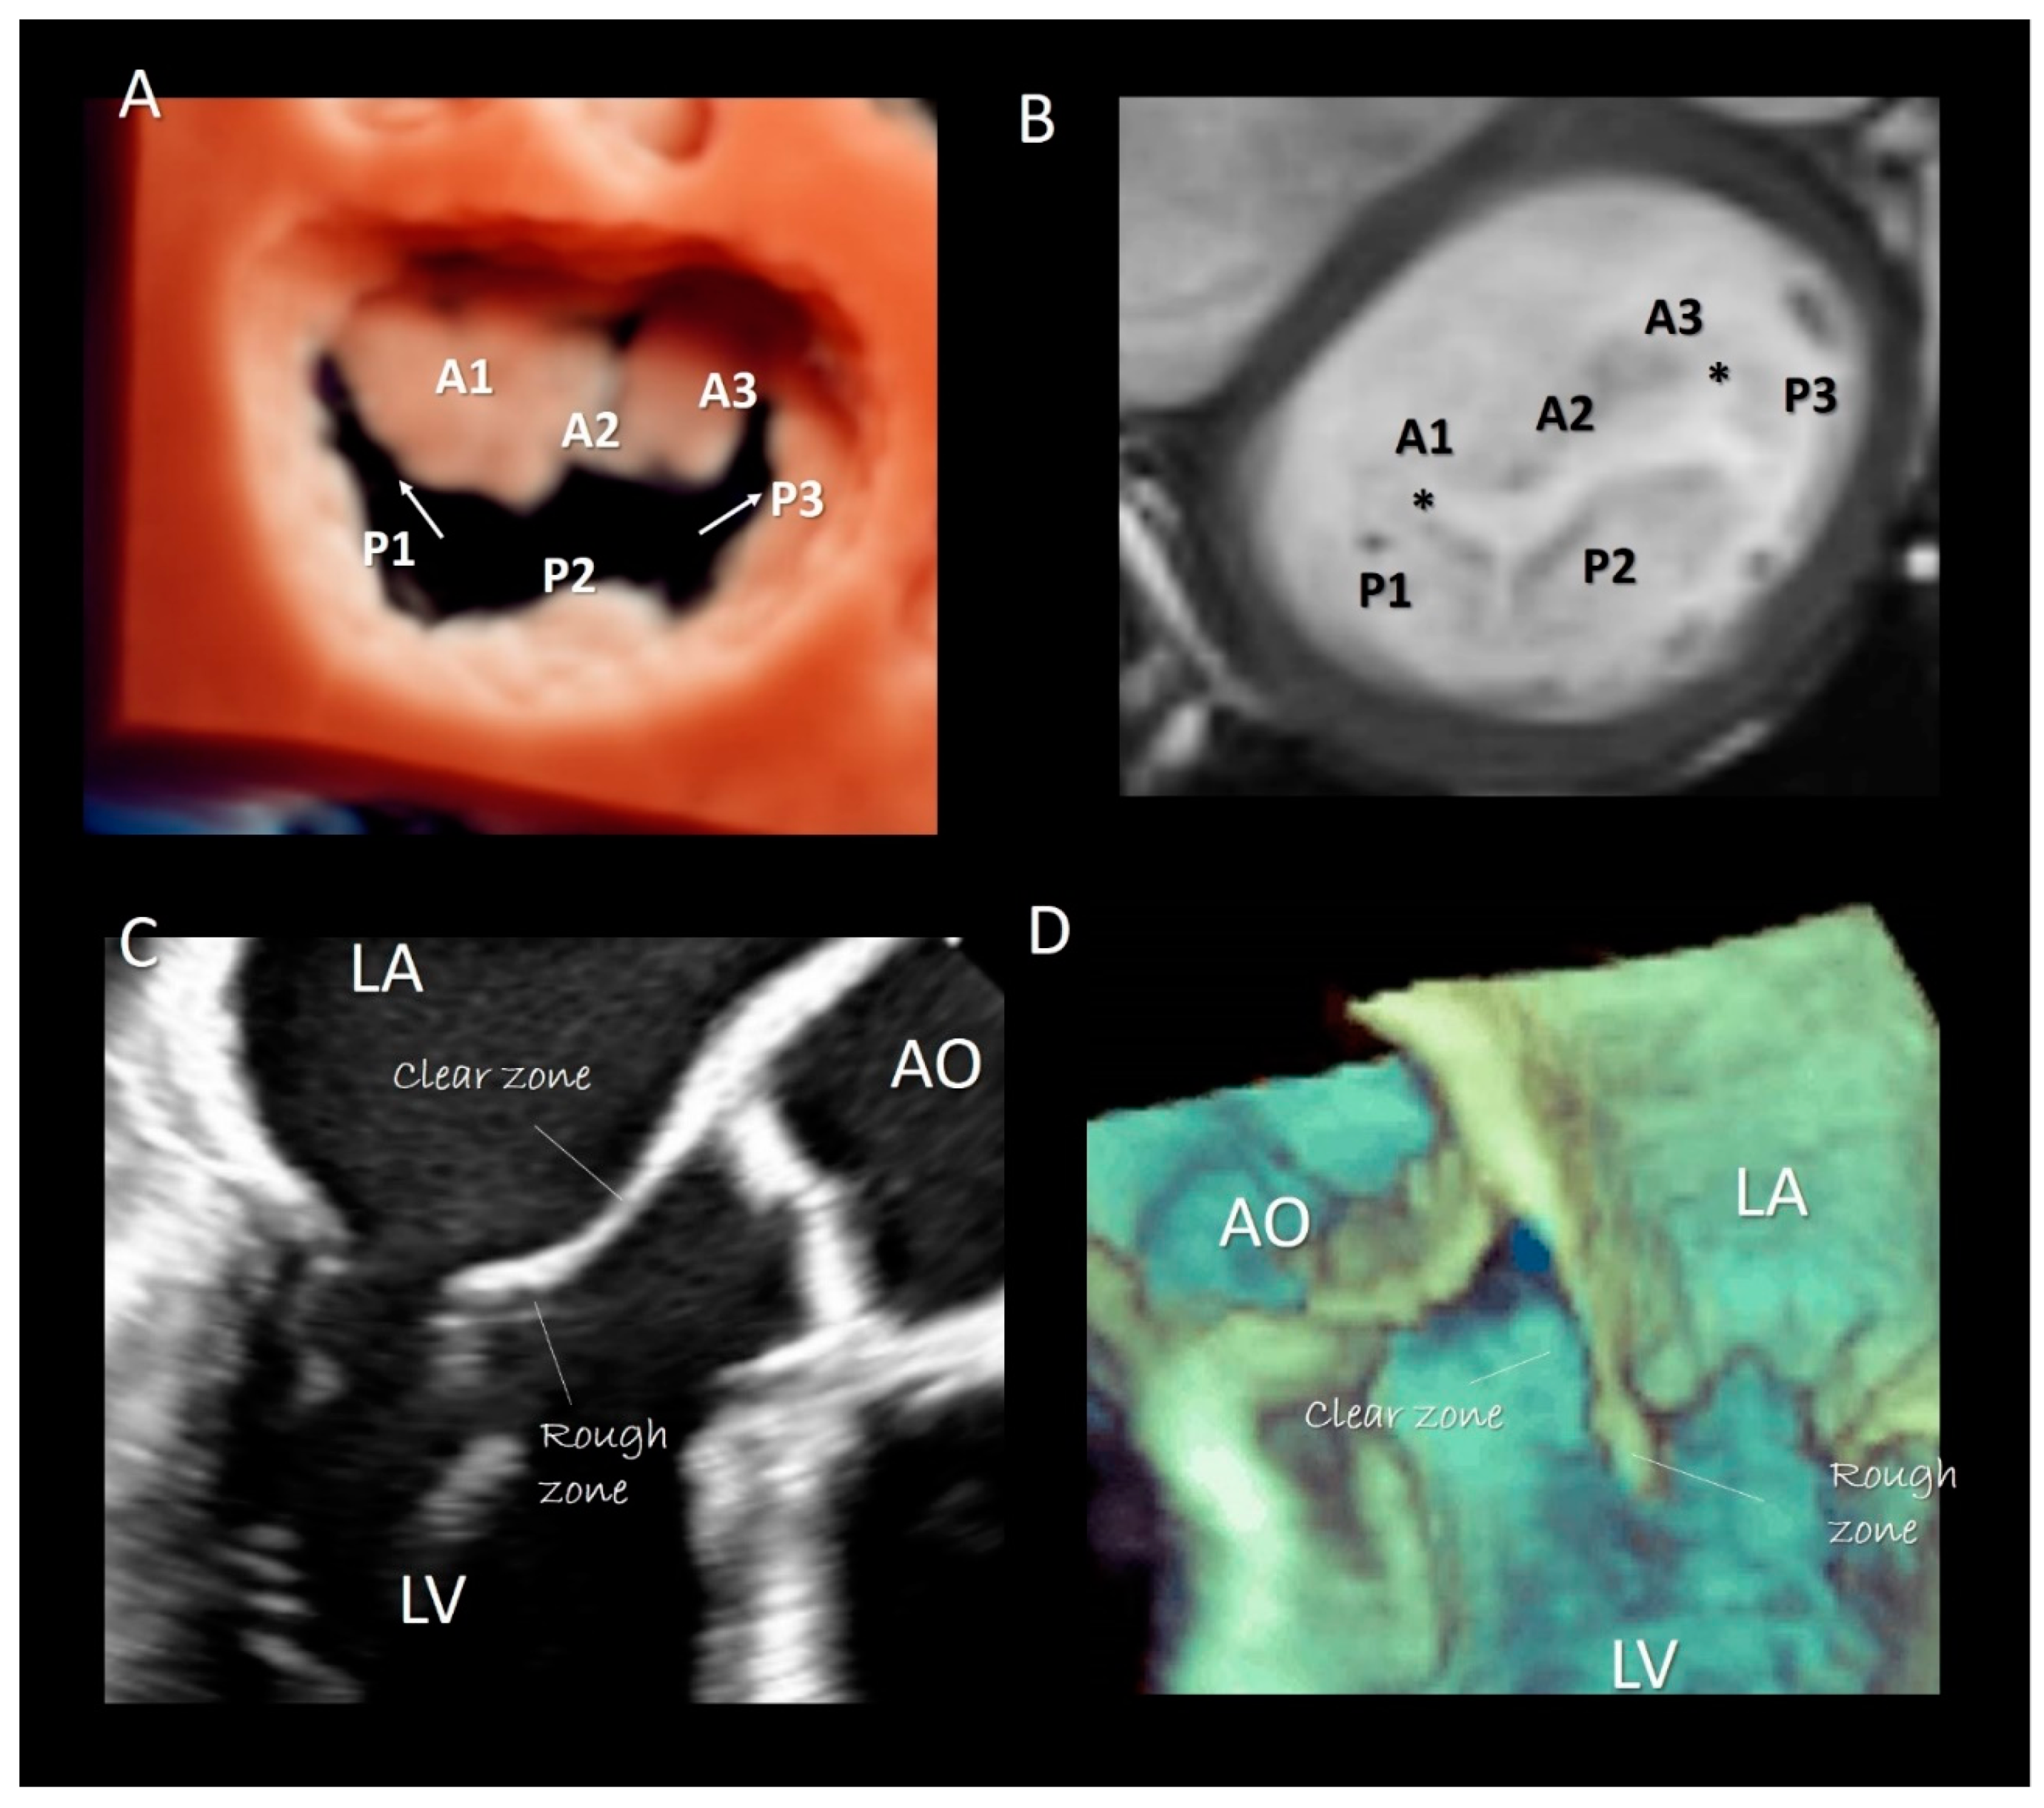

3. Mitral Leaflets

Imaging Techniques